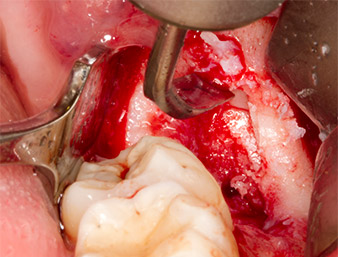

Incision du sulcus

Fig. 3 : L’incision du sulcus démarre au milieu de la dent 36 (LL6), avec extension distale sur le ramus ascendant.

Le tissu recouvrant le reste radiculaire n’est pas entièrement ossifié et est essentiellement constitué de tissu de granulation modifié par l'inflammation (Fig. 4).

Tissu de granulation

Fig. 4 : Deux écarteurs Lagenbeck et un raspatoire exposent la zone d’intervention. On aperçoit le tissu de granulation de la première ostéotomie non totalement cicatrisée.